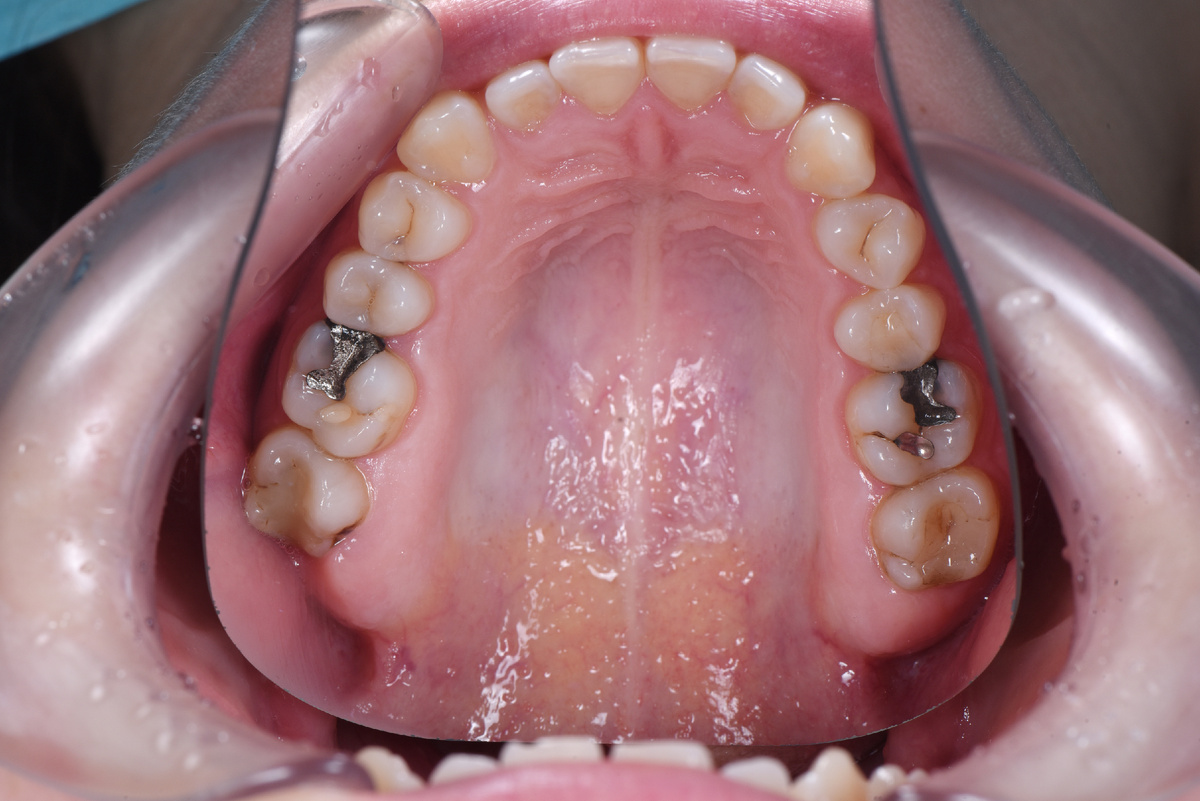

Клиническая картина

Мария обратилась для санации ротовой полости перед ортодонтическим лечением: для выявления и лечения кариеса, замены старых пломб, если это необходимо.

Во время первичного осмотра мы обнаружили у пациентки амальгамовые пломбы👇

Амальгамовые пломбы на зубах 1.6 и 2.6